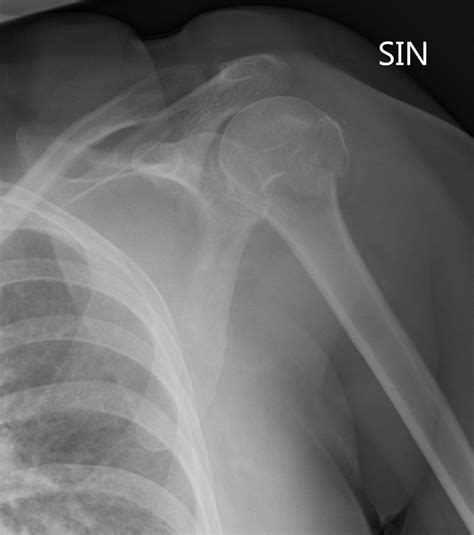

Diagnosis of Inferior Shoulder Dislocation

Diagnosing an inferior shoulder dislocation involves a combination of physical examination and imaging tests. The diagnostic process typically includes:

• Physical examination: A healthcare provider will assess the shoulder for deformity, swelling, and range of motion.

• X-rays: Imaging tests can confirm the dislocation and rule out fractures or other injuries.

• CT scan or MRI: These advanced imaging techniques may be used to evaluate the extent of the injury and plan treatment.

Accurate diagnosis is crucial for determining the appropriate course of treatment and ensuring a successful recovery.

• inferior shoulder dislocation xray

• inferior shoulder dislocation xr